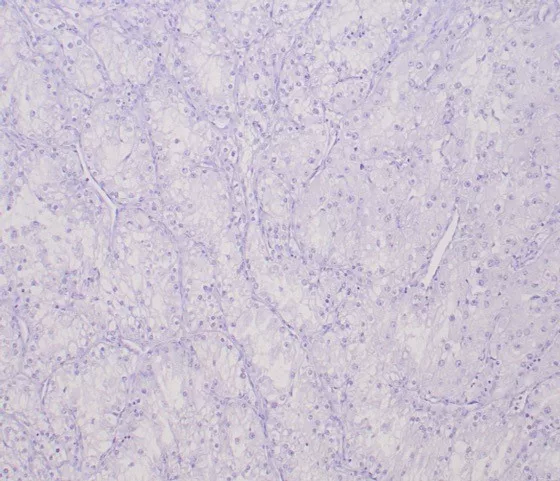

IHC analysis of formalin-fixed, paraffin-embedded human clear cell RCC. Negative tissue control using TFE3/6849R at 2ug/ml in PBS for 30min RT. HIER: Tris/EDTA, pH9.0, 45min. 2°: HRP-polymer, 30min. DAB, 5min.